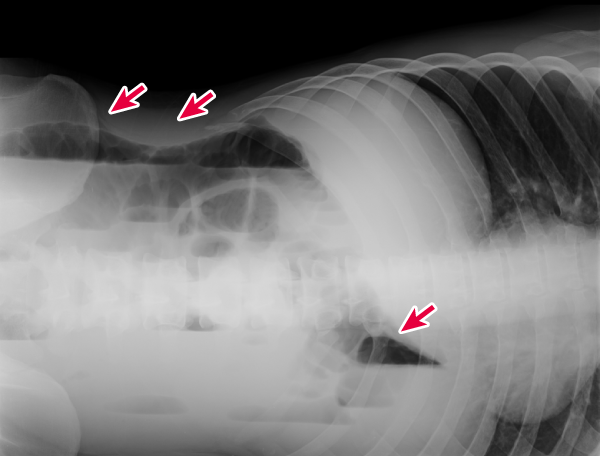

図1:症例1(Aさんの腹部単純X線画像(左側臥位)

図1 症例1(Aさん)の腹部単純X線画像(左側臥位)

研修医:まずは見るからに状態の悪そうなAさんをアセトアミノフェン点滴で鎮痛しながらX線撮影に行ってもらって,と…,ん?側臥位の腹部単純X線でニボー(図1があるからイレウスっぽいなあ,早く消化器科にイレウス管挿入を依頼しなきゃ.Bさんはくも膜下出血の除外のために頭部CTをとって問題がなければ筋緊張性頭痛としてNSAIDsを処方して明日神経内科を受診してもらおうっと.